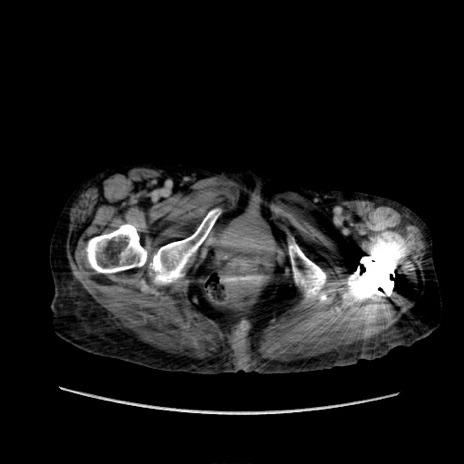

症例31(横断像)

【症例】80歳代 女性

【主訴】腹部膨満感

【現病歴】他院にて肝硬変にてフォロー中。1週間前から便秘、腹部膨満感、臍部腫瘤あり受診となる。

【既往歴】肝硬変

【身体所見】腹部膨隆あり、皮膚変化なし、疼痛なし。

【データ】WBC 4600、CRP 0.25